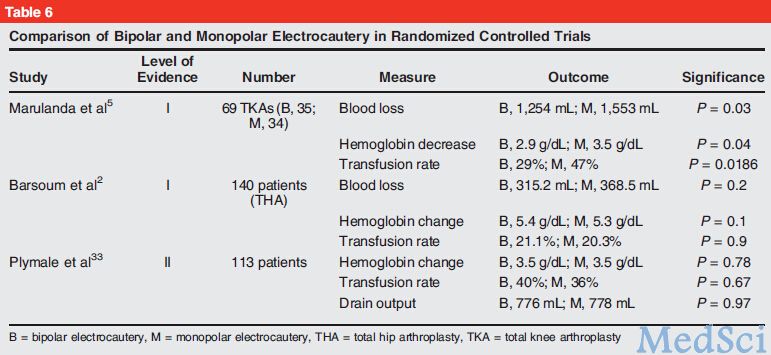

Jaaos 全膝置换术中的血液管理策略 Medsci Cn

Jaaos 全膝置换术中的血液管理策略 Medsci Cn